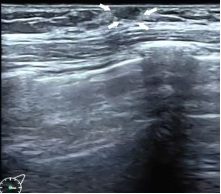

Tanner I期 仅有乳头凸起

(箭头所指为乳头)